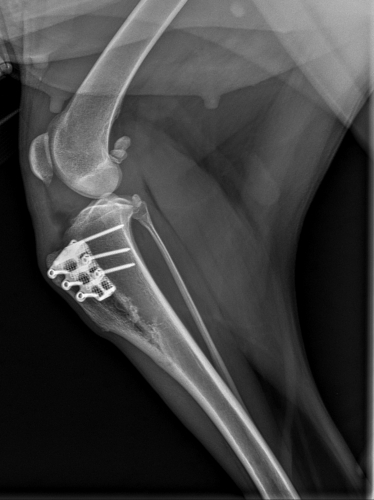

Heute abschließendes Kontroll-Röntgen. Die kleine Sehnenentzündung, welche im letzten Röntgenbild noch erkennbar war, ist vollkommen abgeklungen. Laani ist als geheilt entlassen worden mit den Worten unserer großartigen Tierärztin: „Frohe Weihnachten!“

Heute Kontrolluntersuchung zur vollsten Zufriedenheit unserer Tierärztin absolviert. Wenn man das Röntgenbild sieht, wird sofort klar, warum nun für 6 Wochen kurze Leine verordnet ist. Da muß so einiges zusammenwachsen und ausheilen. Der Knochen wurde gespalten und langsam aufgedehnt, damit die Patellarsehne das Kreuzband ersetzen kann, und das Teil, welches fast aussieht, wie eine Haarspange, wurde dazwischen gesetzt. Der Plan ist, daß der Spalt bald wieder zu wächst.

Das Kreuzband wurde repariert, der Meniskus entfernt. Für die nächste Zeit lesen wir folgende Instruktionen: „6 Wochen Ruhe – kurze Leine – kein Toben, auch nicht zu Hause oder im Garten“. Bekümmert schaut sie aber schon drein, weil ihr geliebtes Sofa unzugänglich ist...